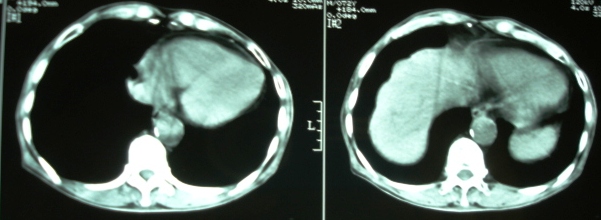

m/72y,皮肤巩膜黄染6个月。

ct意见:1、胆总管结石并肝内胆管、胰管扩张。

2、胆囊结石并胆囊炎。

胆总管结石左侧高密度影是什么?

1)支持楼主意见。2)胆总管结石左侧高密度也应该是胆总管结石。

1)支持楼主意见。2)胆总管结石左侧高密度可能是胆囊管结石。